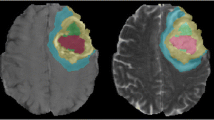

Hypermethylation of the O6-methylguanine-DNA-methyltransferase (MGMT) promoter in glioblastoma (GBM) is a predictive biomarker associated with improved treatment outcome. In clinical practice, MGMT methylation status is determined by biopsy or after surgical removal of the tumor. This study aims to investigate the feasibility of non-invasive medical imaging based “radio-genomic” surrogate markers of MGMT methylation status.

The imaging dataset of the RSNA-ASNR-MICCAI Brain Tumor Segmentation (BraTS) challenge allows exploring radiomics strategies for MGMT prediction in a large and very heterogeneous dataset that represents a variety of real-world imaging conditions including different imaging protocols and devices. To characterize and optimize MGMT prediction strategies under these conditions, we examined different image preprocessing approaches and their effect on the average prediction performance of simple radiomics models.

We found features derived from FLAIR images to be most informative for MGMT prediction, particularly if aggregated over the entire (enhancing and non-enhancing) tumor with or without inclusion of the edema. Our results also indicate that the imaging characteristics of the tumor region can distort MR-bias-field correction in a way that negatively affects the prediction performance of the derived models.